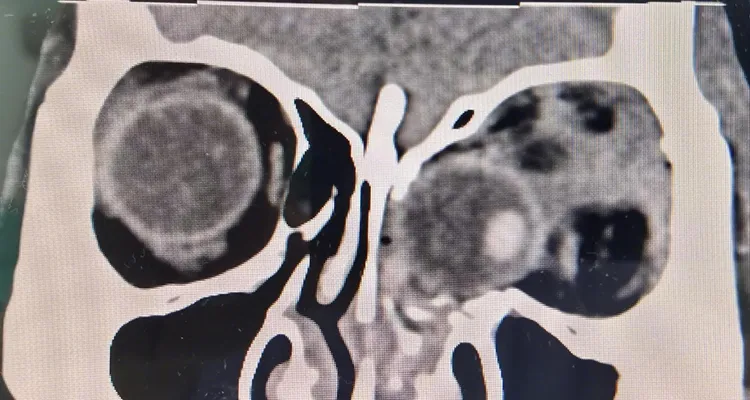

綜合陸媒報導,眼科副主任醫師楊夏指出,「傷者入院時,我們檢查發現其左眼眶及眼球在高墜傷中受到嚴重衝擊,導致左側眼眶內側壁及眼眶下內側壁爆裂性骨折,眼球脫位嵌頓入鼻腔內卡於左側篩竇內和上顎竇內上方,眼球周圍佈滿骨折碎片,眼球變性並且視神經扭曲」。

楊夏醫師說明,經仔細查看影像資料,考慮到傷者受傷時間不到48小時,越早將嵌頓的眼球復位到眼眶內,才有搶救左眼視功能的可能性,於是決定立即為其進行緊急手術搶救傷眼。經過近4小時的微創手術切口,女患者脫位入鼻腔的眼球成功復位到左眼眶內,外觀並未留下手術疤痕。

影像資料圖。翻攝微博